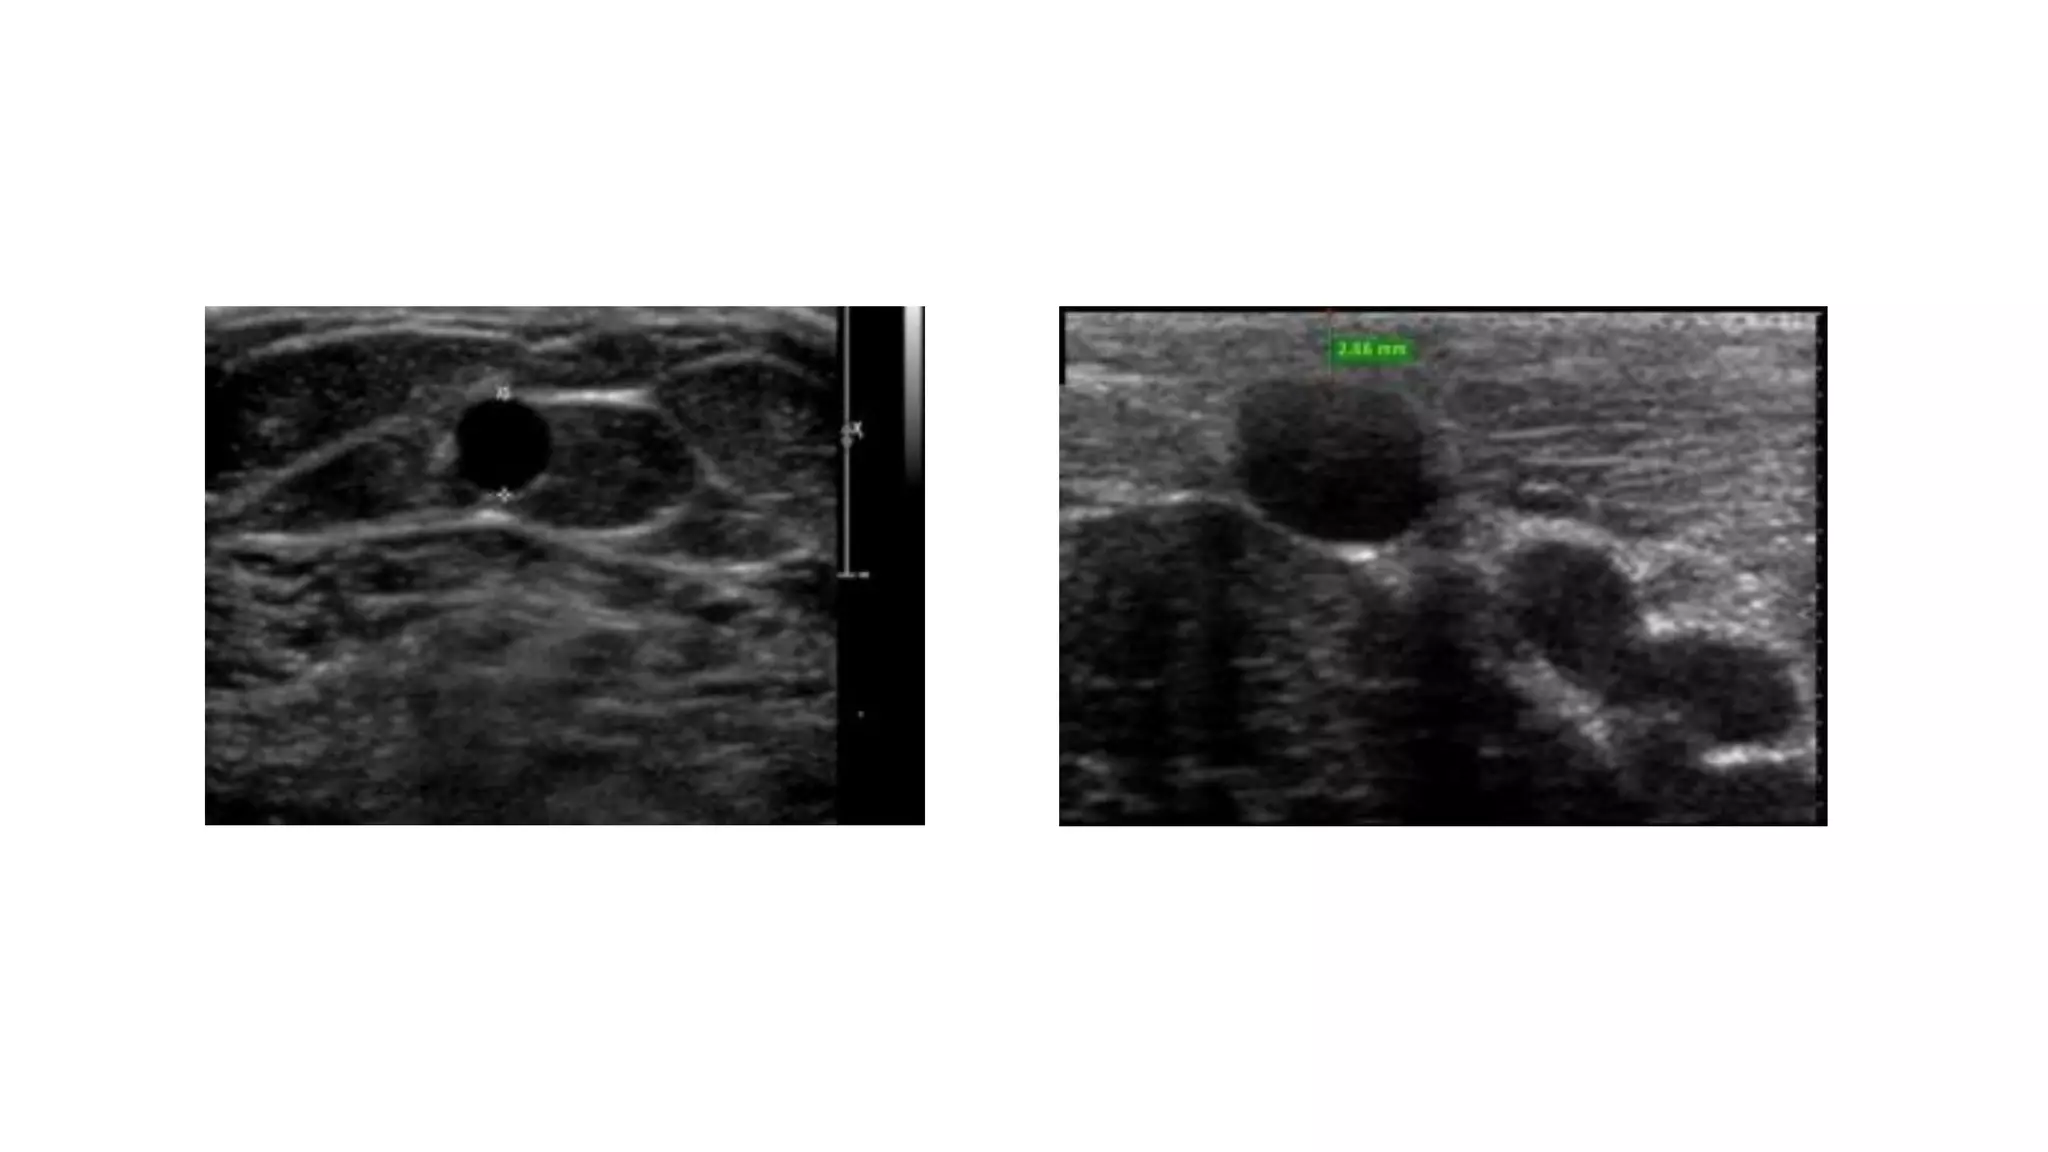

Ultrasound vascular mapping uses ultrasound to examine arteries and veins in the arms before dialysis access placement. It assesses vessel diameter, wall characteristics, blood flow, compressibility, and identifies the best vessels. The mapping examines arteries for internal diameter and wall appearance, uses Doppler to evaluate blood flow, and may check for calcification. It also assesses superficial arm veins for caliber, depth, wall appearance, distensibility, course, patency, and presence of collaterals to identify the best vessel options for dialysis access. A vein mapping worksheet is used to report the ultrasound findings.